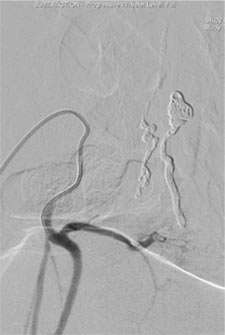

Figure 2: Spinal Dural AVF

Unlike the vascular malformation on or in the spinal cord, dural or epidural AVFs (Figure 2) are an acquired condition, and are commonly discovered in mid 50s males. The symptoms include progressive weakness and numbness in the lower extremities, bowel bladder disturbance, back pain, and sexual dysfunction.

MRI and CT can detect spinal vascular malformations. However, spinal catheter angiography is oftenrequired to further classify the lesion. Making an accurate diagnosis / classification is the first step to compose the best management plan for the lesion.